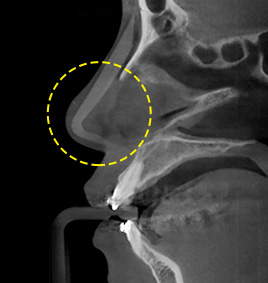

กรณีที่ 3เมื่อใช้ซิลิโคนและผนังกั้นโพรงจมูกคด

ปรับแต่งกระดูกโพรงจมูกและผนังกั้นโพรงจมูกที่คดและสอดซิลิโคนเข้าไป